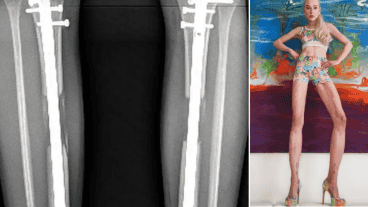

Theresia Fischer, quien protagonizó "Celebrity Big Brother" de Alemania, se sometió a dos cirugías para alargar sus piernas. Ahora miden un metro ochenta de largo.

El proceso de alargamiento de piernas requiere un procedimiento doloroso en el que un médico rompe el fémur en cada una de las piernas del paciente e inserta clavos metálicos extensibles.

La cirugía también implica un largo proceso de recuperación que incluye un dolor "implacable" que estira los nervios, los músculos y el tejido de las piernas hasta un "grado casi insoportable", según el informe de GQ.